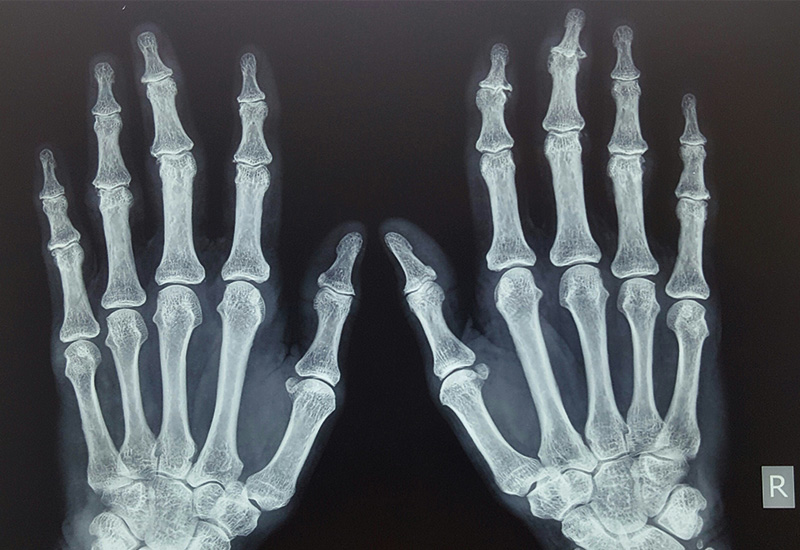

Die EULAR-Empfehlungen, wie gehabt gemäß den EULAR SOPs aus dem Jahr 2014 entwickelt, bieten sowohl auf der Basis von Expertenmeinung als auch wissenschaftlicher Evidenz eine Up-to-date-Anleitung zum Management der Handarthrose.

Nun die spezifischen Empfehlungen: (1) Schulung und Training in ergonomischen Prinzipien, zu Art und Umfang der Aktivität sowie dem Gebrauch von Hilfsmitteln sollten jedem Patienten angeboten werden. (2) Übungen zur Verbesserung von Funktion und Muskelstärke sowie zur Schmerzreduktion sollten bei jedem Patienten erwogen werden. (3) Eine Orthose sollte zur symptomatischen Linderung bei Patienten mit Rhizarthrose erwogen werden. Eine Langzeitanwendung wird befürwortet. (4) Topische werden gegenüber systemischen Therapien aus Sicherheitsgründen präferiert. Topische NSAR sind die erste topische pharmakologische Therapie der Wahl. (5) Orale Analgetika, speziell NSAR, sollten für eine limitierte Zeitdauer zur Schmerzlinderung in Erwägung gezogen werden. (6) Bei Patienten mit Handarthrose kann Chondroitinsulfat zur Schmerzlinderung und Funktionsverbesserung eingesetzt werden. (7) Intraartikuläre Glukokortikoid-Injektionen sollten nicht generell bei allen Patienten eingesetzt werden, können aber bei schmerzhaften Interphalangeal-Gelenken in Erwägung gezogen werden. (8) Patienten mit Handarthrose sollten nicht mit konventionellen oder biologischen DMARDs behandelt werden. (9) Eine Operation sollte bei Patienten mit strukturellen Abnormitäten erwogen werden, wenn andere Therapien keine ausreichend effektive Schmerzlinderung bieten. Eine Trapezektomie sollte bei Patienten mit Rhizarthrose erwogen werden und eine Arthrodese oder Arthroplastie bei solchen mit einer Interphalangealarthrose. (10) Das Langzeit-Follow-up von Handarthrose-Patienten sollte an deren individuelle Bedürfnisse angepasst werden.